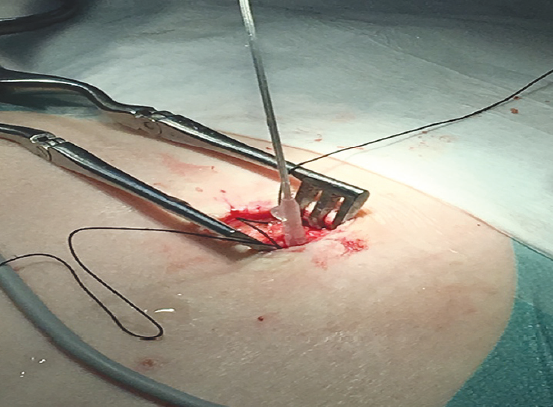

At stage 1, an electrode was implanted in root S3. After a short skin incision (up to 2.0 cm) before aponeurosis, pockets were formed by stratification of subcutaneous fatty tissue from it to lay the electrode loops and site of its connection with a temporary extension cable. To install the electrode, we used a standard Tuohy needle, which was directed almost perpendicular to the foramen S3 to the bone. Thereafter, at a 60° angle to the surface and about the same in relation to the midline, the needle was further moved deeper into the tissue until the feeling of loss of resistance and the tip of the needle appeared at the lower edge of the sacrum in a lateral projection (Fig. 3). After removal of the stylette, an electrode was drawn along the needle lumen. When positioned correctly, it should have a craniocaudal direction in lateral projection and a mediolateral direction in a direct radiograph (see Fig. 3).

Fig. 3. The x-ray images in the lateral and direct projections show a Tuohy needle installed in the S3 hole through which the electrode is conducted

Рис. 3. На рентгенологических снимках в боковой и прямой проекциях изображена игла Туохи, установленная в S3 отверстие, по которой проведен электрод

In addition to radiological support, neurophysiological control, particularly intraoperative electrical stimulation, was used to confirm the accuracy of the electrode location. With an adequate electrode position, stimulation with amplitude of less than 2.0 mA causes plantar flexion of the great toe and reduction in the anal sphincter.